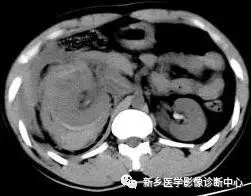

5 肝破裂出血

文章图片